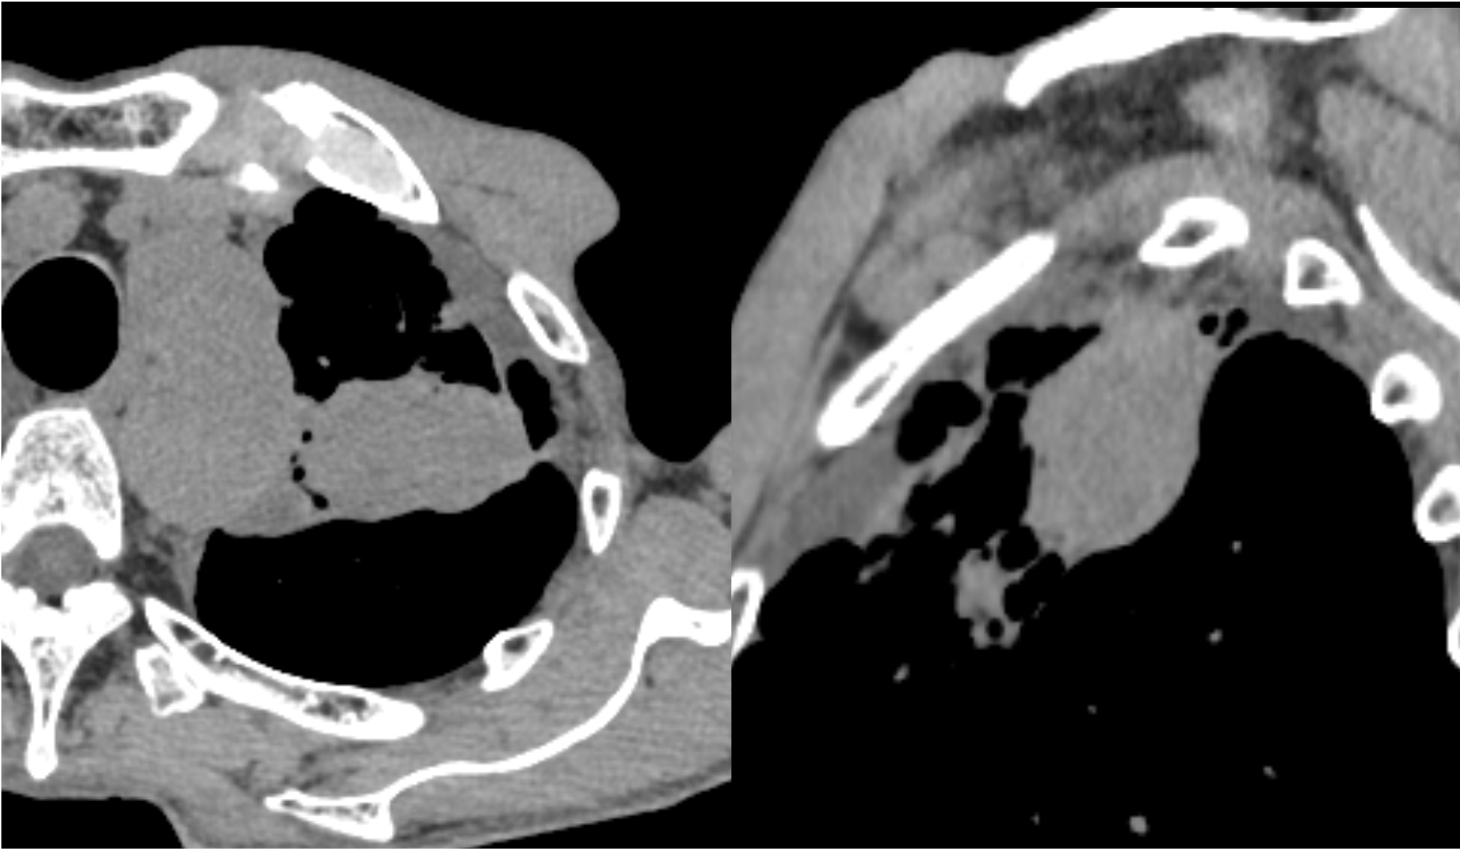

図3.造影CT後期相(Virtual Monoenergetic Image 40keV表示)

40keV表示では、腫瘤の造影効果が図4に比して強調されている。

図4.造影CT後期相(Virtual Monoenergetic Image 70keV表示)

70keV表示は、一般的な後期相の造影効果を表している。

図5.造影CT後期相(Virtual Monoenergetic Image 100keV表示)

100keV表示では、造影効果は減弱しているが、ノイズは軽減している。

図6.keVと腫瘤のROI値の関係を示したグラフ

keVを下げるほど、腫瘤の吸収値は大きく上昇する。

今回使用したフォトンカウンティングCTであるNAEOTOMαは、従来型のCTと異なる点として、仮想単色X線画像(Virtual Monoenergetic Image: VMI)が撮影後に使用できる点が挙げられる。70keVでの表示が基本設定だが、40keVの低エネルギー画像、100keV以上の高エネルギー画像も任意に取得できる。体重が少ない患者や腎機能低下患者で造影剤量を減量せざるを得ない状況でも、低エネルギー画像によって造影効果を持ち上げ、評価を可能にする。また金属アーチファクトが強い部位などでは、高エネルギー画像を取得し、アーチファクト低減に役立てることも可能である。またkeVの値によってどの程度の吸収値を呈するか、グラフ化することも容易である。留意している点としては、ヨード量を担保するために体重別に造影剤使用量、造影剤注入速度を変更して運用している。